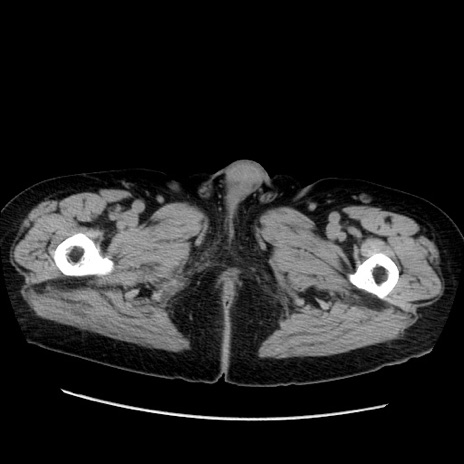

冠状断像